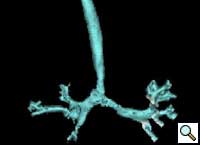

The patient underwent division of the right aortic arch through a left posterolateral thoracotomy (3rd intercostal space) approach. The right aortic arch was posterior, giving rise to the right common carotid and subclavian arteries. The left aortic arch was anterior, giving rise to the left common carotid and left subclavian arteries (Figure 4). The ligamentum arteriosum was attached to the left aortic arch and the left pulmonary artery. The ligamentum arteriosum was divided.